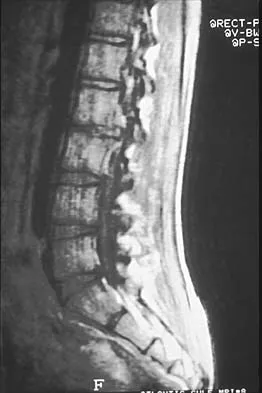

An 18-month-old boy has 45 degrees of kyphosis in the thoracolumbar spine secondary to type I congenital kyphosis. Examination reveals that he is neurologically intact, and an MRI scan shows no evidence of intraspinal pathology. Management should consist of

Surgery is indicated for congenital kyphosis once the deformity reaches a certain size or if significant progression is documented. In a young patient with a relatively small deformity, the treatment of choice is isolated in situ posterior fusion and postoperative immobilization. If an adequate posterior fusion can be obtained, an epiphyseodesis effect can be generated, allowing the remaining anterior growth to cause some correction. Because there is no evidence of neurologic compression and the deformity is less than 50 degrees, anterior surgery is not indicated. There is no role for bracing in the management of congenital kyphosis. Winter RB: Congenital Deformities of the Spine. New York, NY, Thieme-Stratton, 1983, pp 229-261.